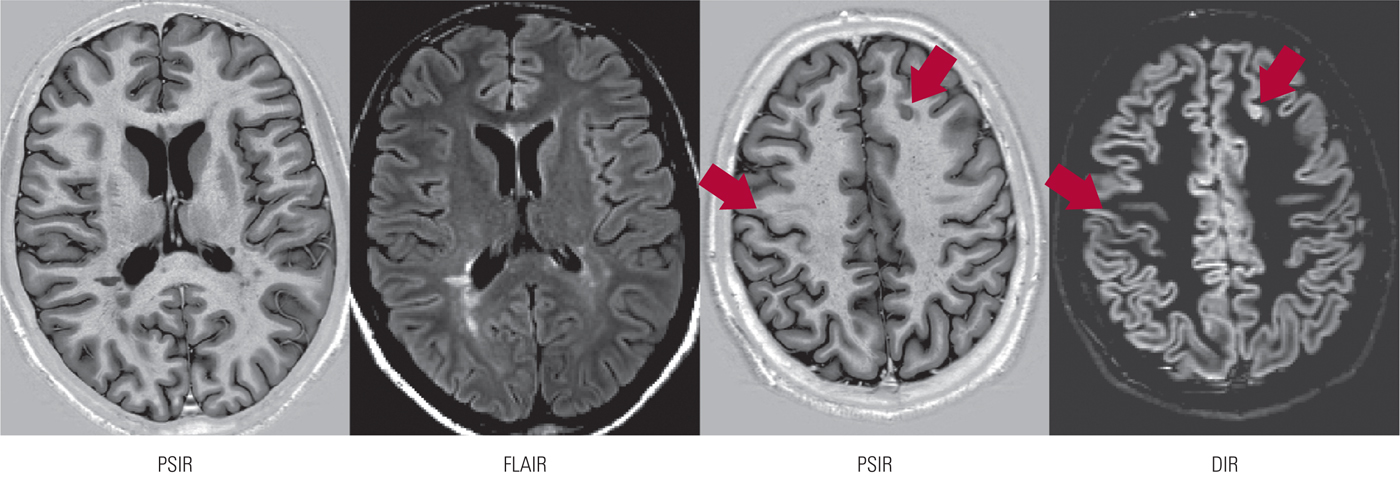

Magnetic resonance imaging (MRI) has played a crucial role in advancing the understanding and treatment of the disease by making it possible to study MS pathology in vivo. MRI visualises macroscopic lesions in white and grey matter (Fig. 1). Of these, T2 hyperintensities represent heterogeneous pathology (oedema and inflammation, demyelination and remyelination, gliosis and axonal loss), whereas T1 hypointensities represent demyelination and axonal loss. Using diffusion-based techniques such as diffusion tensor imaging (DTI), and other techniques such as magnetisation transfer and spectroscopy, subtle abnormalities in the ‘normal-appearing brain tissue’ (NABT) can be detected and quantified. Abnormalities in the individual tracts connecting different brain regions can be studied using tractography, another DTI-based technique. It is also possible to quantify white and grey matter atrophy.

FIG 1 Cortical and periventricular lesions in multiple sclerosis, identified by three magnetic resonance imaging techniques: PSIR, phase-sensitive inversion recovery; FLAIR, fluid-attenuated inversion recovery; DIR, double inversion recovery.